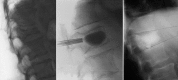

Cement reinforcement for the treatment of osteoporotic vertebral fractures is efficient mean with high success in pain release and prevention of further sintering of the reinforced vertebrae; however, the technique does not allow to address the kyphotic deformity. Kyphoplasty was designed to address the kyphotic deformity and help to realign the spine. It involves the percutaneous placement of an inflatable bone tamp into a vertebral body. Restoration of VB height and kyphosis correction is achieved by inflation of the bone tamp with liquid. After deflation, a cavity is created that eases the cement application. The potential of kyphosis reduction is given in fresh fractures with a range of 0-90% for height restoration and absolute correction of the kyphotic angle of 8.5 degrees. The cavity formation, on one hand, and the different cementing technique leads to lower risk for cement extravasation. An alternative method for kyphosis correction represents the so-called lordoplasty where the adjacent vertebrae are reinforced first and with the cannulas in place acting as a lever the reduction of the collapsed vertebra can be performed. The results with respect to kyphosis correction are superior in comparison with a kyphoplasty procedure.